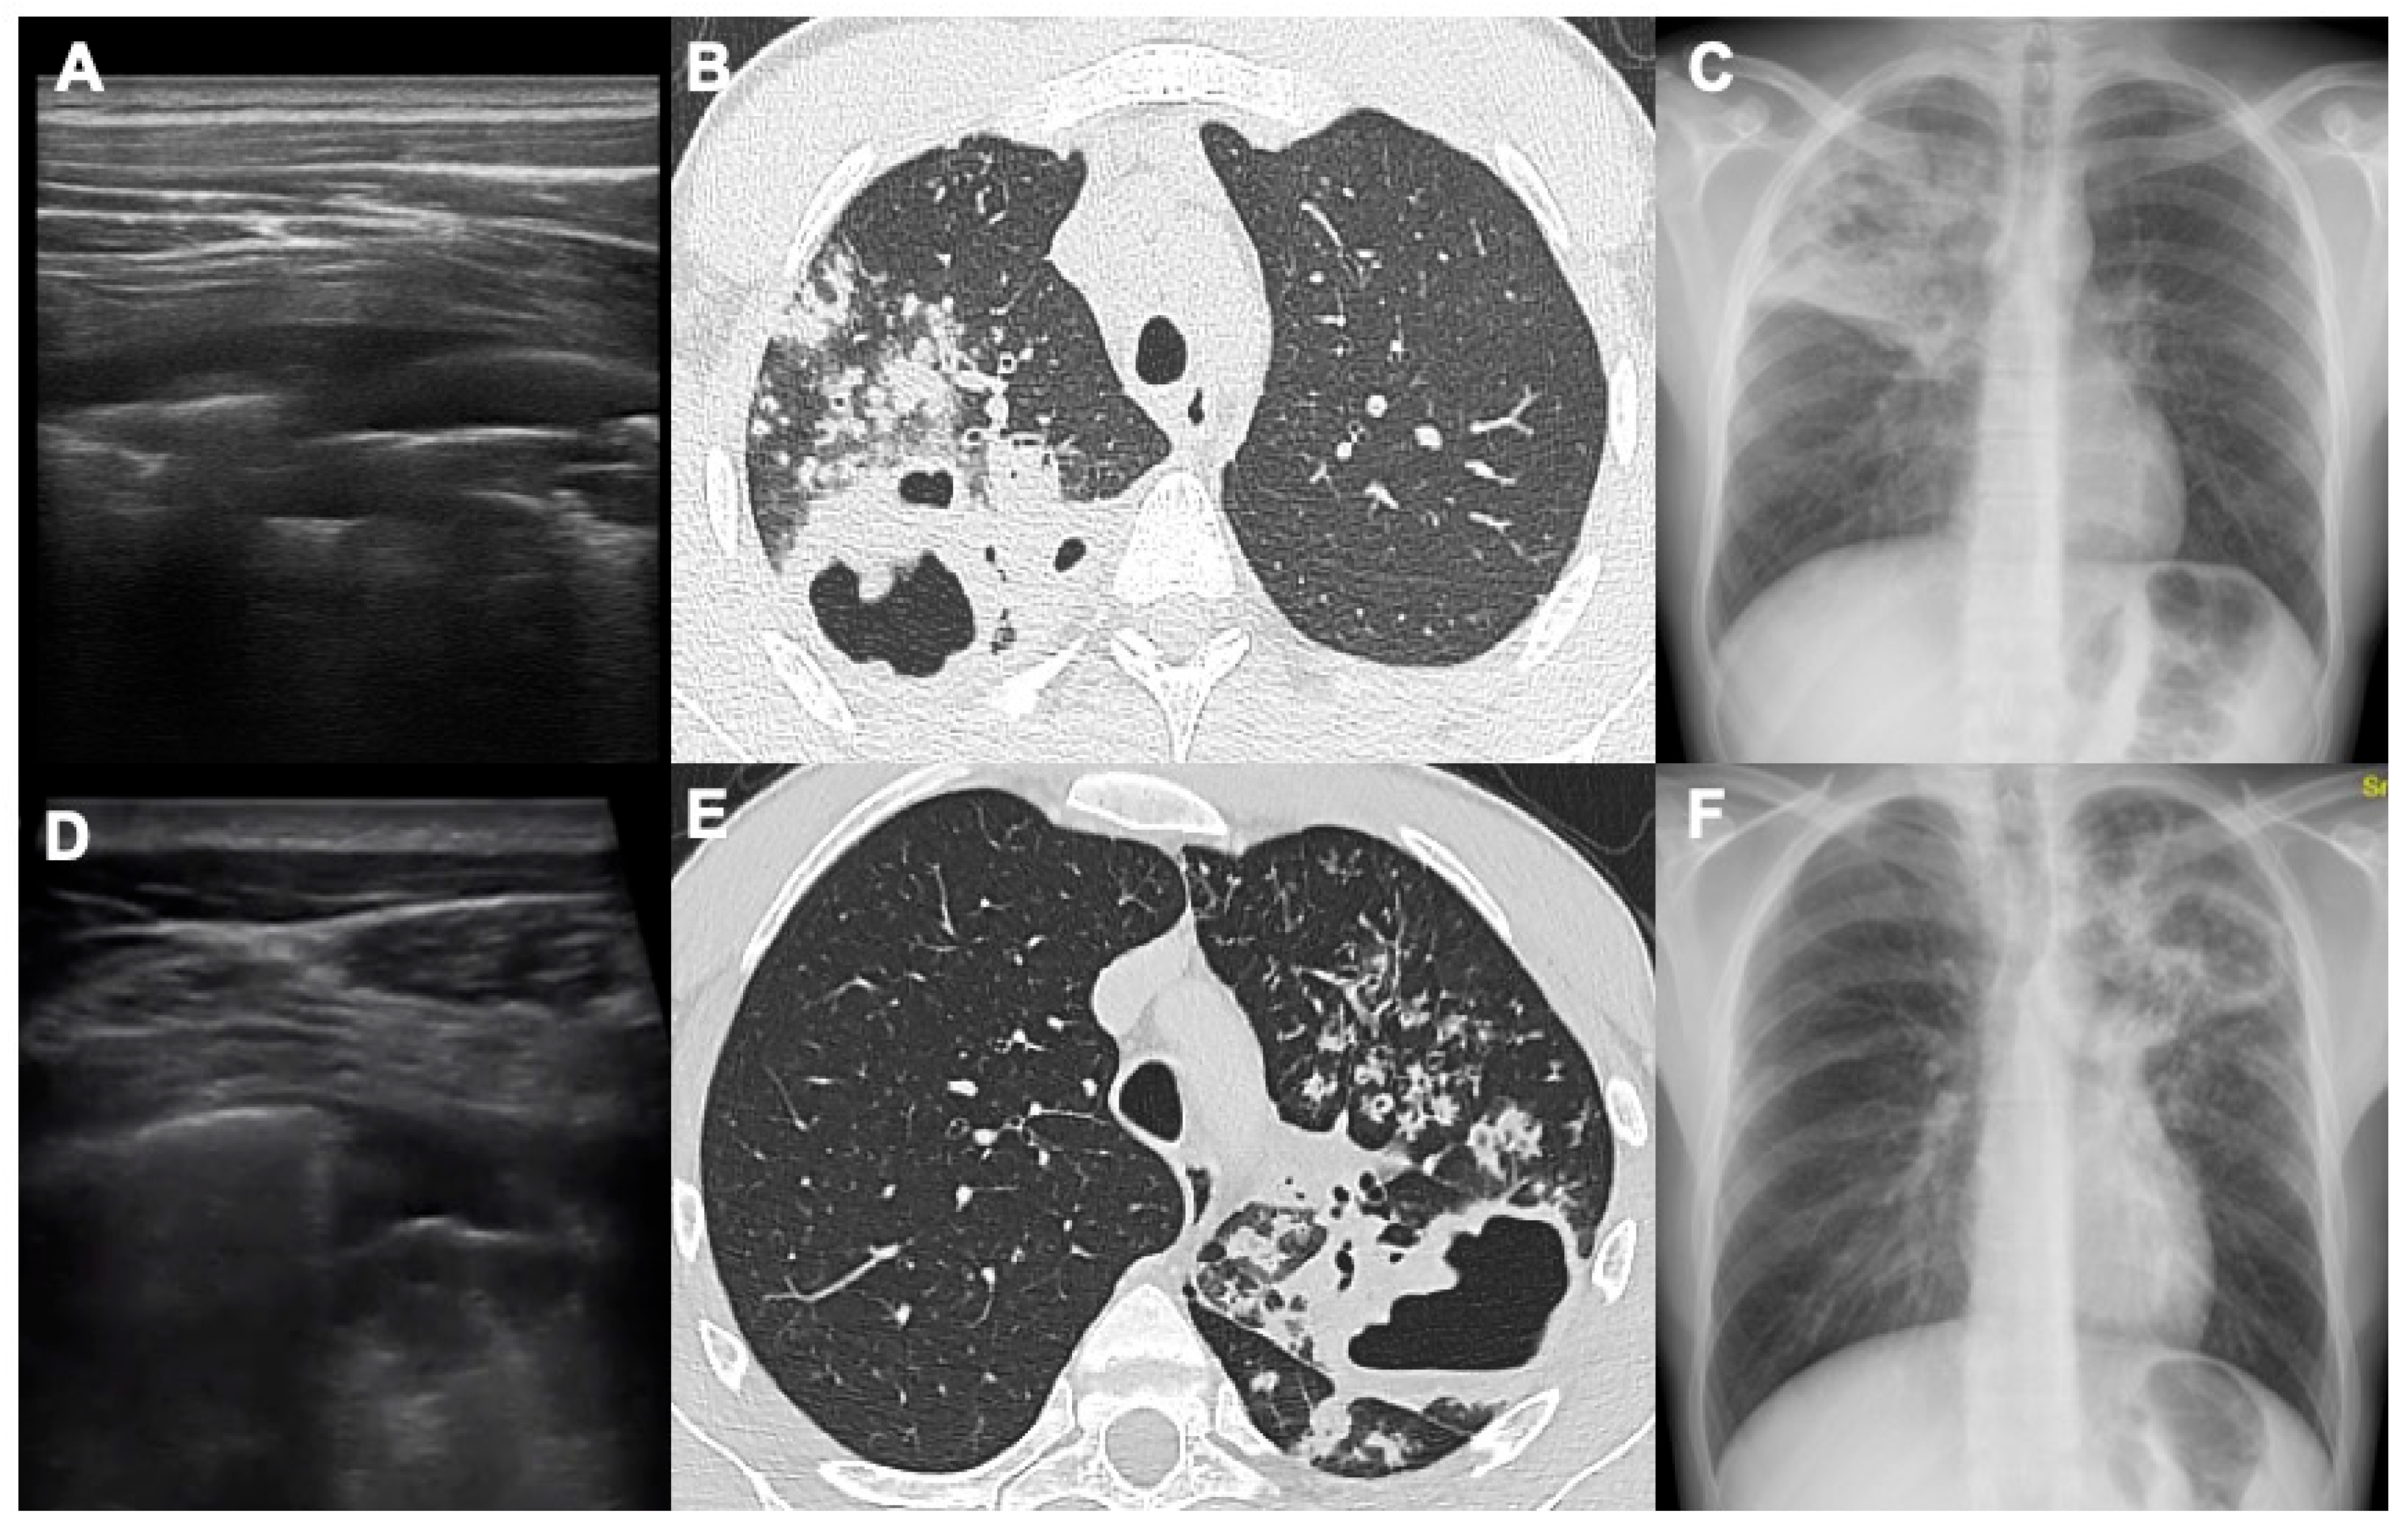

Parenchymal Cavitations in Pulmonary Tuberculosis: Comparison between Lung Ultrasound, Chest X-ray and Computed Tomography

| Computed tomography | 32/58 (55.2%) | 6/24 (25%) | 0.112 |

| Chest X-ray | 23/58 (40%) | 4/24 (16.7%) | 0.135 |

| Lung ultrasound | 11/58 (19%) | 4/24 (16.7%) | 0.838 |